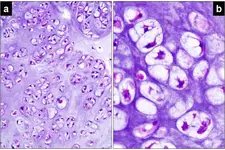

Diz Kıkırdak Belirtileri ve Tedavisi Diz kıkırdağı, diz ekleminin düzgün çalışabilmesi için kritik bir yapı oluşturur. Kıkırdak, eklem yüzeylerini kaplayarak sürtünmeyi azaltır ve hareket sırasında şok emici bir görev üstlenir. Ancak, çeşitli nedenlerden dolayı diz kıkırdağında hasar meydana gelebilir. Bu yazıda, diz kıkırdağında oluşabilecek belirtiler, bu belirtilerin nedenleri ve tedavi yöntemleri detaylı bir şekilde ele alınacaktır. Diz Kıkırdak Hasarının Belirtileri Diz kıkırdağında meydana gelen hasar, çeşitli belirtilerle kendini gösterebilir. Bu belirtiler, hasarın ciddiyetine ve nedenine bağlı olarak değişiklik gösterebilir. Yaygın belirtiler şunlardır:

Diz Kıkırdak Hasarının Nedenleri Diz kıkırdak hasarının birçok nedeni vardır. Bu nedenler arasında şunlar sayılabilir:

Diz Kıkırdak Hasarının Tanısı Diz kıkırdak hasarının tanısı, genellikle bir ortopedi uzmanı tarafından konulur. Tanı sürecinde şu yöntemler kullanılabilir: